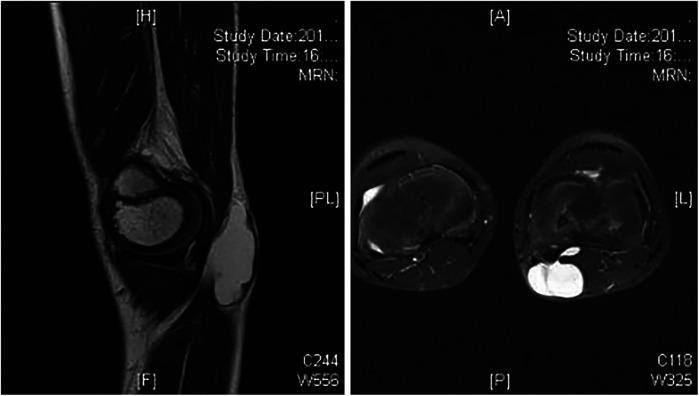

Abstract Image